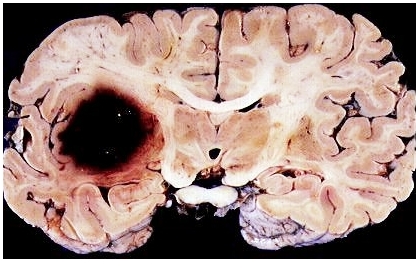

뇌출혈

뇌출혈은 뇌로 혈액을 공급하는 혈관이 터져서 뇌로 가는 혈액 공급이 중단되는 질환입니다. 뇌출혈의 75% 정도는 그 원인이 고혈압인 것으로 알려져 있습니다. 혈압이 높아져서 뇌의 혈관 약한 부분이 터지는 것이죠. 과로와 스트레스가 원인이 될 수 있습니다.

뇌혈관은 뇌 조직에 산소와 영양분을 공급해 주는 역할을 하는데, 이 혈관이 고혈압으로 장기간 압력에 노출되면 혈관에 변화가 생기는데요. 이런 상황에서 과도한 흥분이나 긴장, 과로 등의 요인이 겹치면 혈압이 올라가게 되고, 혈관이 이 압력을 견디지 못해서 터질 수 있는 것입니다. 특히, 당뇨나 고지혈증이 있는 환자들에게 더 흔히 발생할 수 있는 질환이 뇌출혈이기도 합니다.